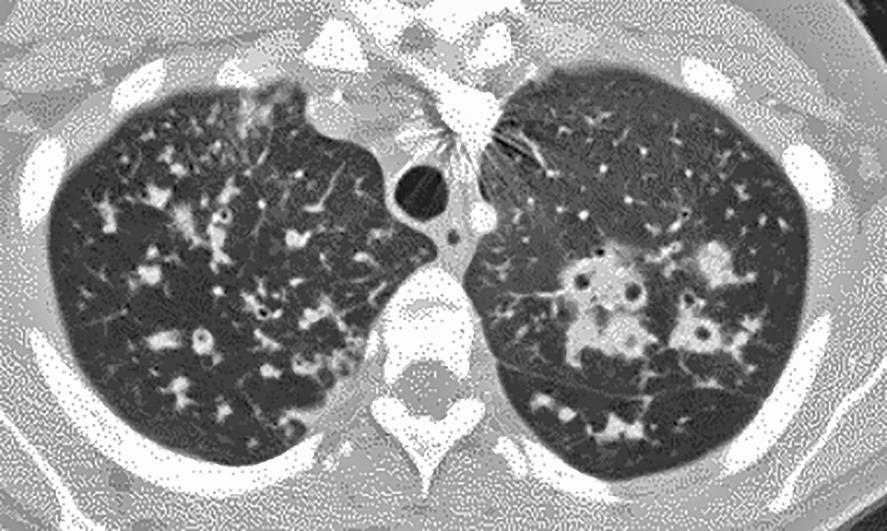

Seul un scanner thoracique haute résolution confirme le diagnostic anatomique : augmentation permanente et irréversible du calibre des bronches sous-segmentaires, cylindriques, variqueuses ou kystiques, localisées à un lobe ou diffuses. On élimine une autre cause de toux chronique comme un cancer bronchique. Toux, expectoration, infections bronchiques répétées + bronchectasies au scanner définissent le syndrome bronchectasique.